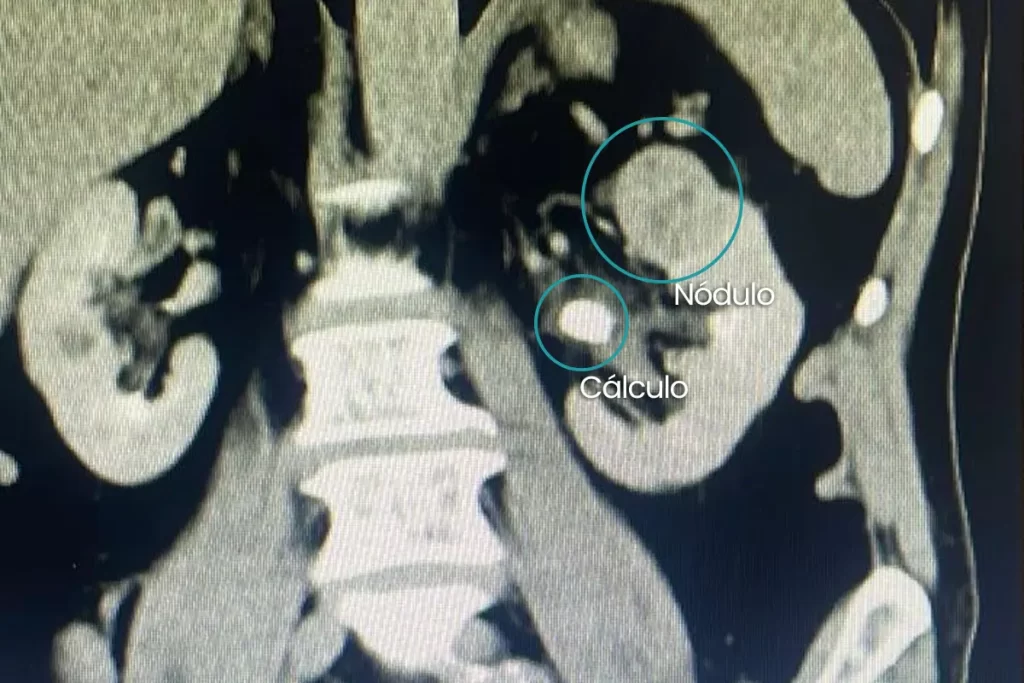

Durante a investigação pré-operatória, a tomografia computadorizada revelou duas condições distintas no mesmo rim: um nódulo renal de aproximadamente 3 cm na porção superior e um cálculo de 1,3 cm localizado na pelve renal. A combinação desses achados exigiu uma estratégia cirúrgica precisa e avançada.

Paciente ICR.T - tomografia com cálculo e nódulo

Tomografia computadorizada do paciente